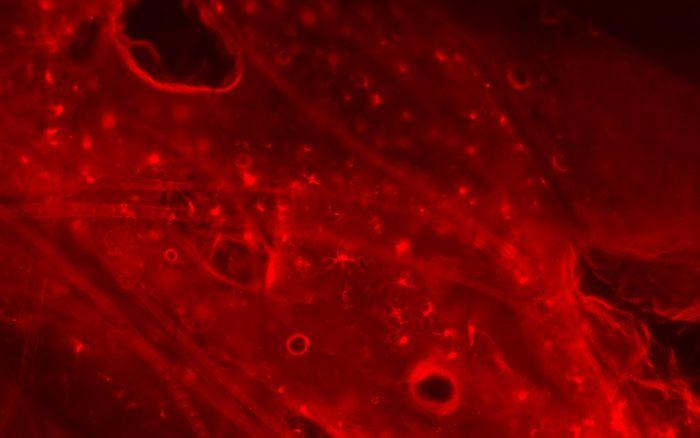

移植片対宿主病は、血液悪性疾患に対する治療として行われる骨髄移植の副作用として、ドナー骨髄細胞がレシピエント臓器組織を攻撃することで起こります。攻撃対象が皮膚粘膜の場合は、びらん化する丘疹・紅斑が生じます。一方、ランゲルハンス細胞は、皮膚免疫を司る表皮常在抗原提示細胞で、炎症性皮膚疾患では増加しますが、移植片対宿主病ではドナー骨髄細胞の標的となって消失します。ランゲルハンス細胞の機能については、接触過敏反応において炎症を惹起する、炎症を抑制する、有意な関与はないといったように、相反する説があり、皮膚免疫学における一つの命題となっています。

本研究では、骨髄移植によって惹起する全身性の移植片対宿主病モデルマウスに加え、皮膚粘膜に移植片対宿主病を発症させたモデルマウスを用いて、皮膚病変におけるランゲルハンス細胞の機能を解析しました。その結果、疾患惹起時にあらかじめランゲルハンス細胞を除去したマウスでは、より重度の皮膚粘膜病変を生じること、さらに、生体外での実験系にて、ランゲルハンス細胞が直接、拒絶反応を引き起こす病原性細胞傷害性CD8 T細胞の増殖を抑制し、そのアポトーシス(細胞死)を誘導することから、ランゲルハンス細胞は、皮膚のいわばゲートキーパーとして、移植片対宿主病の進展を抑制する方向に働いていることが分かりました。